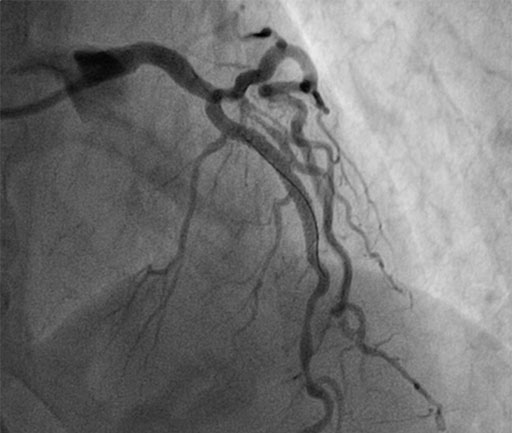

In this case, Dr. Jonathan Hill from Kings College Hospital in London, UK uses the new COMET™ FFR pressure guidewire to assess tortuous multivessel disease and optimize treatment strategy.

• Highly tortuous anatomy, may be difficult to assess invasively

• Tortuosity: FFR wire may be difficult to deliver

• COMET™ FFR wire delivers through highly tortuous vessel

• FFR of 0.88 (not pictured)